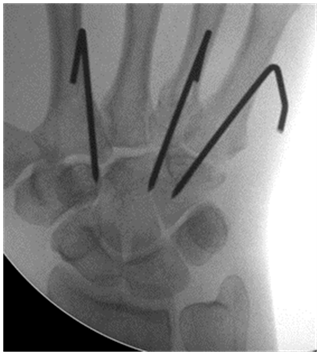

Closed reduction and K-wire

Stabilization of the reduced CMC joints by percutaneous k-wiring is the technique most advocated for in the literature (Figure 6).1,2,5,34,35 Reduction is achieved as described above with traction and counter pressure.1 Once achieved, the dislocated ray is stabilised with percutaneous K-wire(s) passed retrograde from the metacarpal base into the corresponding carpal bone. Oblique, intramedullary, transverse and cross wiring techniques have been described.5 The optimal positioning of K wires is crucial as stability must not be achieved at the compromise of free tendon free gliding.36 The safest corridor for pinning unstable fifth carpometacarpal injuries is 2 cm distal to the joint at an angle of 20–30 degrees to the coronal plane from 10 degrees volar to dorsal to 20 degrees dorsal to volar direction in the sagittal plane.36 In cases of isolated CMC dislocation, a single wire is often passed retrograde from the metacarpal to the corresponding carpal bone and a trans-metacarpal wire is then passed to the normal adjacent ray.5,37 In the case of complete dislocations, some authors advocate stabilization of the second and third CMC only3,5,37 as this is often sufficient to hold the reduction because of the integrity of the intermetacarpal ligaments.37 Use of multiple wires may give a stable construct, but suffers the effects of multiple K wires passing through these small joints, possibly skewering the tendons thus theoretically increasing risk of complications, most notably stiffness.38 Citing this complication with the use of multiple wires, some authors advocate for the use of the fewest necessary wires to minimise the intra-articular damage these wires may have on the small joints.

Figure 6 K wire stabilisation to hold reduction.

The optimum time for retention of the K-wires is varied in the literature. Periods of four to 12 months are reported. The average being 6 weeks. Emphasis is once again made of individualising care to the individual patient and to follow them closely. While risking re-dislocation, early removal has the potential benefit of reducing skin and tendon complications thus improving overall outcome.39 No specific complications have specifically been attributed to prolonged retention of the k-wires.3